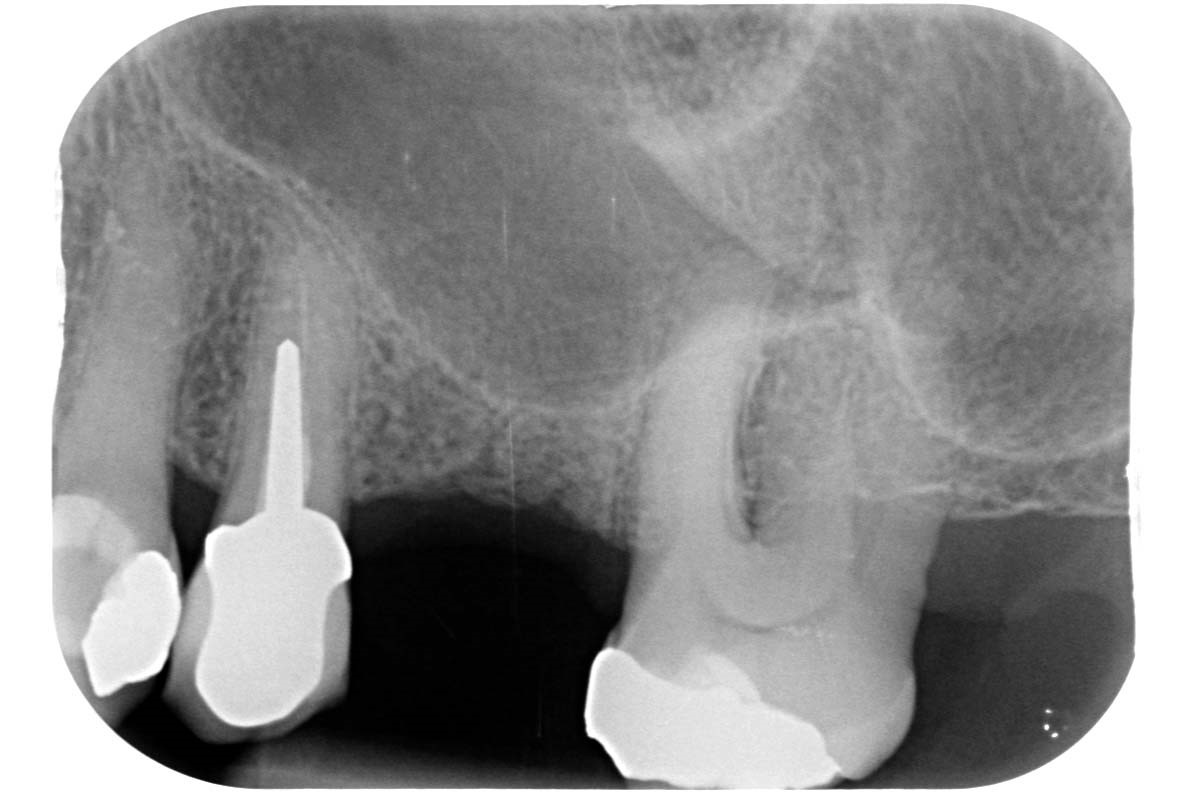

01/35 - Initial x-ray, tooth 25 compromised and to be extractedMaxillary sinus cyst removal using the Crocodile Technique and subsequent lateral sinus lift - Dres. C. Scognamiglio and A. Perucchi